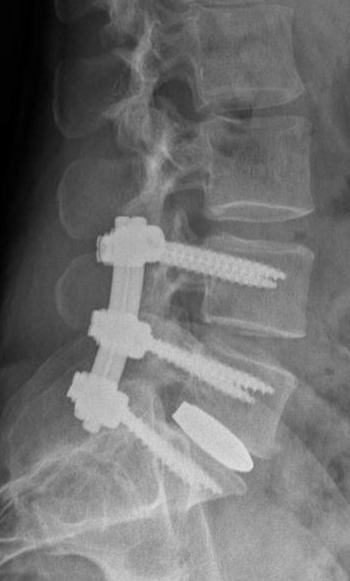

In una artrodesi postero-laterale ci si avvale dell'impianto di barre e viti peduncolari in associazione ad innesto di osso autologo (fig.8), per ottenere una secondaria "artrodesi" fisiologica (ossia una fusione ossea), potendo anche prevedere la stabilizzazione di più spazi contigui.

• Figura 08